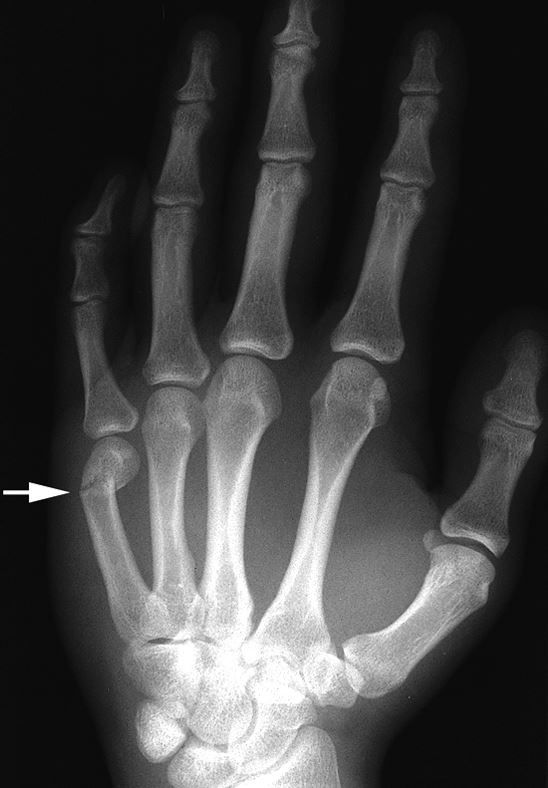

X-ray of a "boxer's fracture"

X-ray of a "boxer's fracture" in the fifth metacarpal. This common hand fracture can cause the knuckle on the affected finger to appear sunken in or angulated.

Reproduced from Johnson TR, Steinbach LS (eds): Essentials of Musculoskeletal Imaging. Rosemont, IL American Academy of Orthopaedic Surgeons, 2004, p. 347.